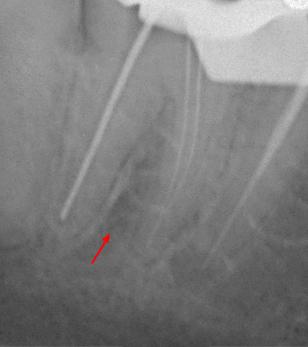

Пациентка 28 лет обратилась с жалобами на приступообразную ночную боль в области нижней челюсти справа.

На жевательной поверхности 47 зуба глубокая кариозная полость в пределах околопульпарного дентина, пульповая камера не вскрыта, зондирование болезненное, перкуссия безболезненная, холодовой тест резко болезненный, после удаления раздражителя болевая реакция продолжается в течении 20-ти секунд.

Диагноз: необратимый пульпит 47-го зуба.

На рентгенологических снимках представлена картина до лечения, диагностический снимок и конечный результат.